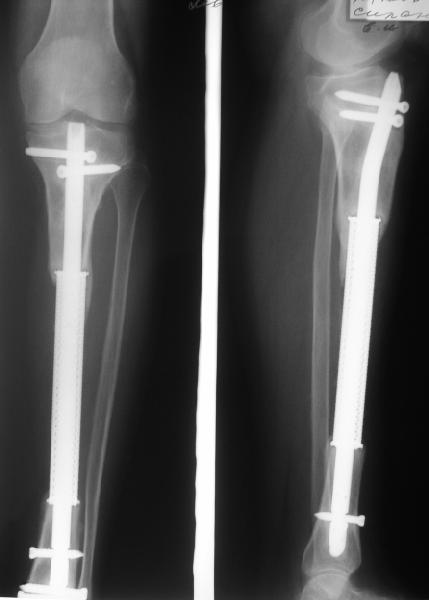

Re: Тяжёлая травма голени, остеомиелит

В приложении рентгенограмма через год после операции.